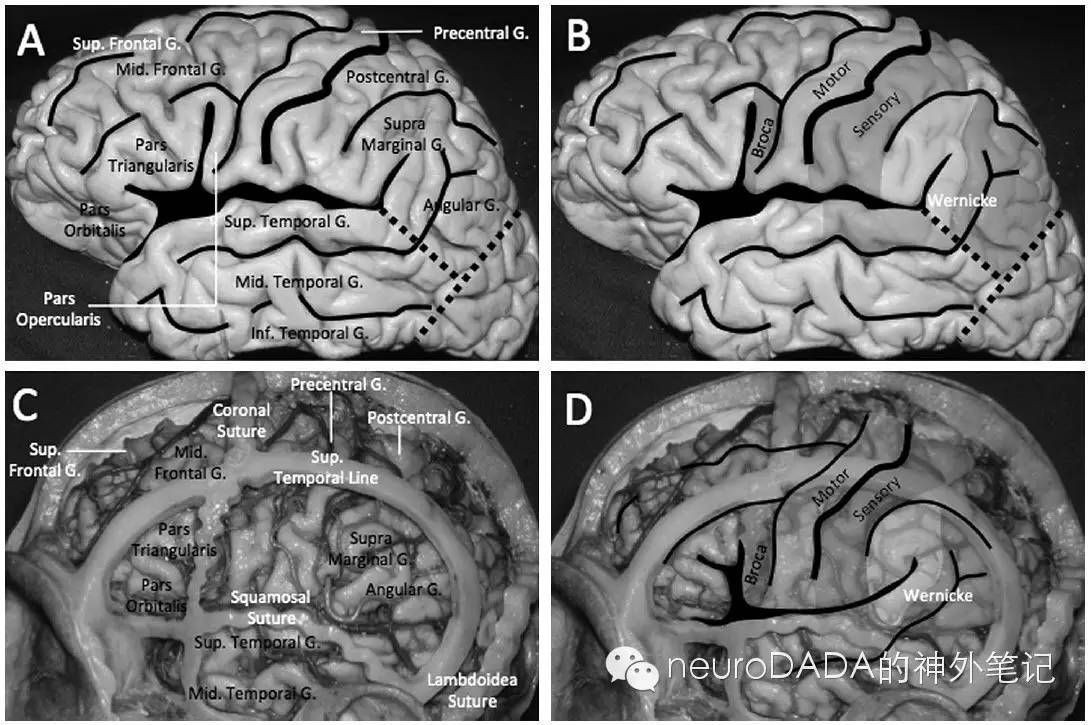

2.颅骨与皮层的关系

4.功能解剖学

方法二,再看根据解剖投影的定位:先把各个基线画好,侧裂与颞上线之间为额下回-侧脑室额角,颞上线对应额下沟-侧脑室顶壁-胼胝体下缘,中央沟则可确定中央后回-中央后沟的大致位置,结合侧裂又可确定缘上回-顶间沟的大致位置。根据术前的读片,病变就位于中央后沟和顶间沟相交的这个深沟内,而这个深沟应该位于途中切口的后方拐角附近。